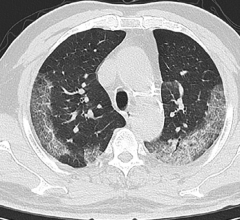

February 26, 2020 — In a study of more than 1,000 patients published in the journal Radiology, chest CT outperformed lab ...

February 26, 2020 — Mount Sinai Health System physicians—the first experts in the country to analyze chest computed ...